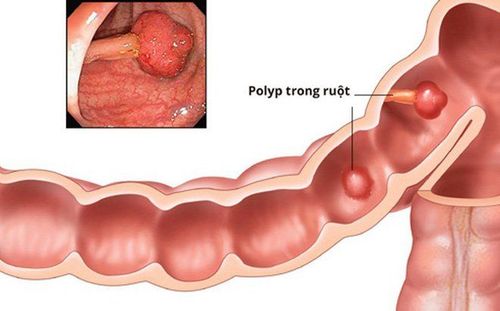

1. Polyp đại tràng là gì?

Polyp đại tràng là một khối nhỏ các tế bào hình thành trên niêm mạc đại tràng (ruột già). Hầu hết các polyp đại tràng là vô hại nhưng qua thời gian, một số polyp đại tràng có thể phát triển thành ung thư đại tràng, gây tử vong khi được tìm thấy ở giai đoạn muộn của nó. Có thể có 1 hoặc nhiều polyp ở đại tràng. Bất cứ ai cũng có thể bị polyp đại tràng.

Polyp đại tràng thường không gây ra triệu chứng. Điều quan trọng là phải tầm soát thường xuyên, chẳng hạn như nội soi đại tràng bởi vì polyp đại tràng phát hiện ở giai đoạn sớm thường có thể được cắt bỏ hoàn toàn và an toàn. Việc phòng ngừa tốt cho ung thư đại tràng là tầm soát polyp thường xuyên.